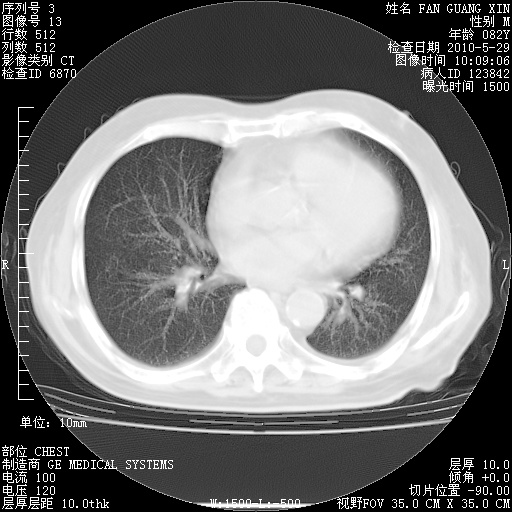

再治疗10天后的肺部CT

再治疗10天后的肺部CT 纵膈窗

从白细胞总数和中性比例看好像合并感染。肺部纹理好像比上次多,支气管炎?其他感染?

阅读此次胸部CT,肺间质渗出性改变较入院时有吸收。目前从体温、白细胞、中性分叶明显增高,肯定存在细菌感染(发生医院感染哦,若无消化道及泌尿系统等感染的依据,肺部感染可能大)。若你院头孢哌酮舒巴坦钠耐药率较高,同意你的方案,若48小时体温仍高,可考虑使用碳青霉稀类抗菌药物,同时可予超声雾化、注意滴数时加大液体量。白蛋白33.30g/L较低哦,需加强营养等支持治疗。